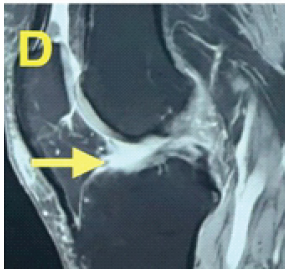

Simultaneous Anterior Cruciate Ligament Avulsion Fracture with Bilateral Posterior Meniscal Root Tears of the Knee: A Case Report

Deem Alsedais , Bader Majed Aljadaan , Hamad H Aldakhil Allah , Abdullah Adel Al-Nasser , Ibrahim Ababtain ………………………………p.222-226

Single-Stage Management of Anterior Cruciate Ligament Tear with Dual Menisci Bony Root Avulsion: A Rare Case Report and Review of Literature

Mukesh Garg , Vishesh Verma

………………………………p.283-289